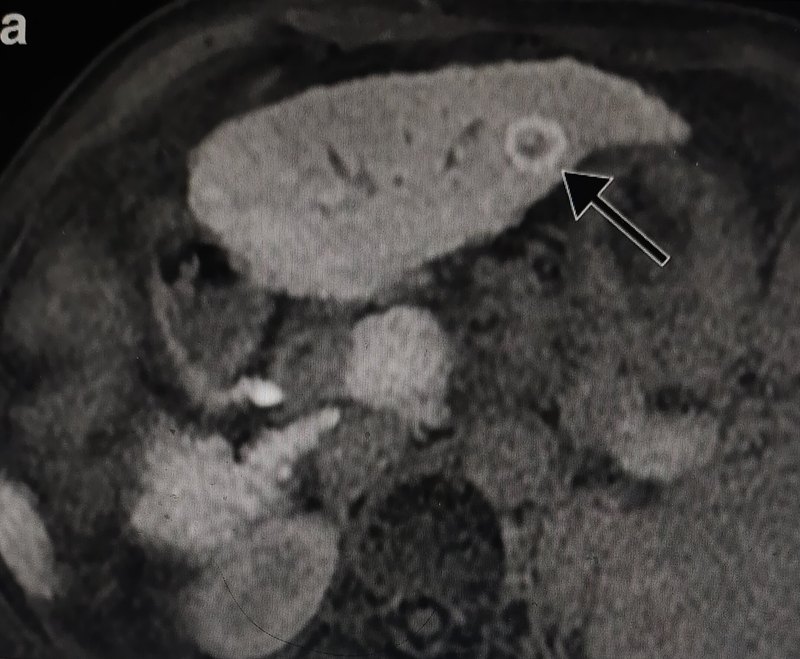

肝臟環(huán)形強(qiáng)化是指肝臟占位病變做CT或MR增強(qiáng)掃描,動(dòng)脈期時(shí)病變外周相對(duì)中央部位呈明顯強(qiáng)化表現(xiàn)。環(huán)形強(qiáng)化是部分肝臟病變特征性的表現(xiàn),在影像報(bào)告描述中并不少見(jiàn)。其病理基礎(chǔ)與病變邊緣腫瘤細(xì)胞代謝活躍、炎性肉芽組織、代償性異常灌注等因素致血供增加有關(guān)。中央?yún)^(qū)低密度(信號(hào))與囊變、壞死、出血、脂肪浸潤(rùn)、纖維化、鈣化有關(guān)。環(huán)形強(qiáng)化病變有很多,既有良性又有惡性病變,大致分為血管性、炎性及腫瘤病變。環(huán)形強(qiáng)化病變大體診斷思路是:觀(guān)察環(huán)壁的均勻性、完整性、是否有壁結(jié)節(jié)及其他輔助征象。下面僅就三種最常見(jiàn)的環(huán)形強(qiáng)化病變的典型表現(xiàn)做簡(jiǎn)單介紹。這三種病變是遇到環(huán)形強(qiáng)化時(shí)首先考慮要排除的。①肝膿腫:環(huán)壁厚度均勻、完整、光滑,門(mén)脈期及延遲期病灶范圍逐漸縮小等。②轉(zhuǎn)移瘤:環(huán)壁不規(guī)則、中斷,或見(jiàn)強(qiáng)化的壁結(jié)節(jié)等。③膽管癌:環(huán)形強(qiáng)化呈向心性充填、鄰近肝包膜收縮、膽管擴(kuò)張等。三種病變均出現(xiàn)彌散受限改變,MR上DWl序列出現(xiàn)高信號(hào),信號(hào)強(qiáng)度膿腫>轉(zhuǎn)移瘤>膽管癌。環(huán)形強(qiáng)化還可見(jiàn)于原發(fā)肝癌、肝轉(zhuǎn)移瘤介入治療(栓塞、消融)術(shù)后復(fù)查影像。術(shù)后炎癥(充血、水腫)、間質(zhì)纖維化,早期(一個(gè)月內(nèi))可出現(xiàn)線(xiàn)狀環(huán)形強(qiáng)化,屬正常反應(yīng),特點(diǎn)是環(huán)壁?。ㄐ∮?mm)、光滑連續(xù)、無(wú)結(jié)節(jié)。此表現(xiàn)可持續(xù)存在3-6個(gè)月。反之環(huán)壁不均勻增厚、出現(xiàn)強(qiáng)化結(jié)節(jié)及鄰近異常灌注,需排除腫瘤殘留及復(fù)發(fā)可能。不同病變的影像征象包括環(huán)形強(qiáng)化經(jīng)常有相互重疊的情況,當(dāng)遇到不典型環(huán)形強(qiáng)化及少見(jiàn)病變時(shí),對(duì)影像科醫(yī)師是不小的挑戰(zhàn),臨床病史包括炎性指標(biāo)、腫標(biāo)等有重要的參考價(jià)值,有些病例不得不依賴(lài)穿刺活檢才能定性。